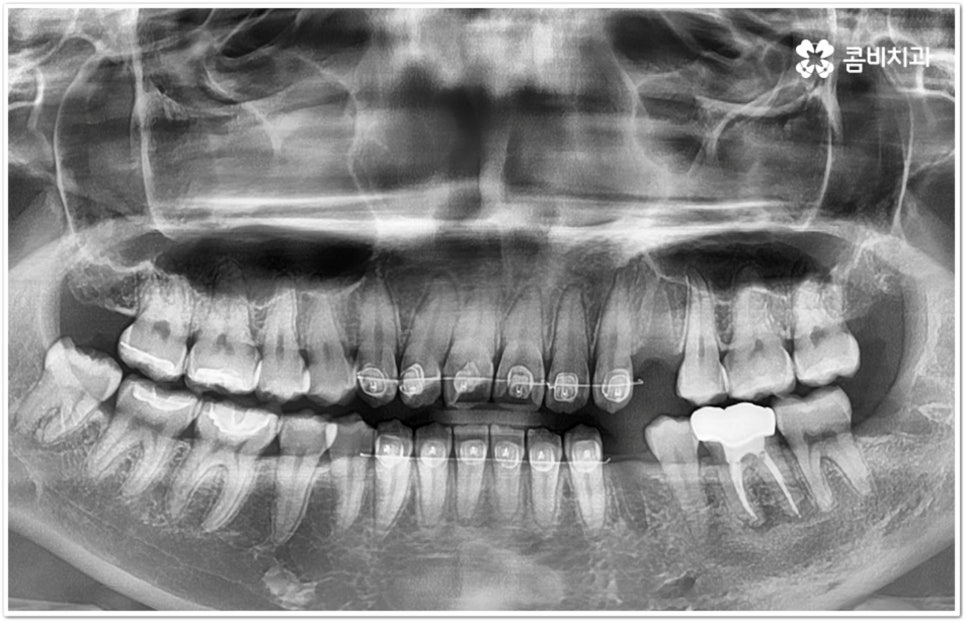

만약 똑바로 자라나고 관리가 용이하며 마주보는 대합치 역시 정상적으로 맹출되었다면 사랑니를 꼭 발치할 필요는 없을 거예요. 그러나 보통 사랑니는 사람의 치아 중에 가장 마지막에 나오는 치아라서 이미 구강 내 공간이 비좁은 상태이기 때문에 비스듬하게 자리를 잡고 일부분만 맹출이 되는 경우가 많이 있어요. 보통 머리가 앞쪽으로 기울어진 근심위로 자리잡는 케이스가 가장 많으며 그 밖에도 치아 머리가 뒤쪽으로 기울어져 있거나 혀쪽, 볼쪽으로 누운 케이스, 아예 옆으로 완전히 누운 케이스 등도 발견되고 있는데요.

잇몸에 반쯤 덮힌 채로 삐뚤게 나온 사랑니는 칫솔질을 제대로 하기 어렵고 위생 관리가 잘 되지 않아 주변 잇몸에 염증이 생기기 쉬우며 어금니까지 충치가 번질 위험이 높아지게 되어 구강 건강 관리 및 예방 차원에서 발치 처치를 해주실 필요가 있어요. 발치 난이도는 사랑니의 경사 각도와 방향 및 치아 뿌리의 길이와 개수, 사랑니 뒤쪽 턱 뼈의 각도 및 형태, 하치조 신경 또는 상악동까지의 거리 등에 따라서 달라질 수 있습니다.

이때 아래사랑니발치 의 경우 아래턱 부근을 지나가는 큰 신경인 하치조 신경을 건드리지 않고 조심스럽게 사랑니만 제거해야 하기 때문에 3D-CT 등 정밀 검진 기계를 통해 사랑니의 매복 위치, 깊이, 각도 등의 상태와 신경까지의 거리 등을 먼저 꼼꼼하게 파악한 후에 발치를 해 줄 필요가 있는데요. 만약 완전히 매복되어 있다면 사랑니 주변에 함치성 낭종이 발생할 수도 있는데 이로 인해 주변 치조골이 파괴되고 어금니 쪽으로 병변이 확산되면 결국 치아를 상실하게 되거나 턱뼈가 약해져서 작은 충격에도 부러지는 현상이 발생할 가능성도 있으므로 될 수 있는대로 치료 시기를 놓치지 않는 것이 중요한 포인트라고 할 수 있어요.

관리하기 까다롭기 때문에 위 아래사랑니발치 를 해 주는 것이 보통이긴 하지만 간혹 사고로 어금니를 상실하거나 유전적으로 어금니가 없으신 분들의 경우 교정 치료를 통해 어금니 대신 사용하는 사례가 있으니 필요하다면 발치 결정 전에 꼼꼼하게 검진을 받아보실 필요가 있어요.

모든 경우에 사랑니가 어금니를 대신할 수는 없으며 사랑니로 어금니를 대체하기 위해서는 사랑니의 상태, 이동 가능 공간, 주변 구조물 및 전체 구강 구조 등 환자분들의 상황을 먼저 면밀하게 살펴본 후 교정 치료 계획을 세심하게 세워 잇몸과 사랑니의 손상 없이 치료할 필요가 있으므로 고난도 과정에 맞게 술자의 높은 숙련도가 요구되는 만큼 노하우가 풍부한 의료진을 선택하시길 권유드리고 있습니다.